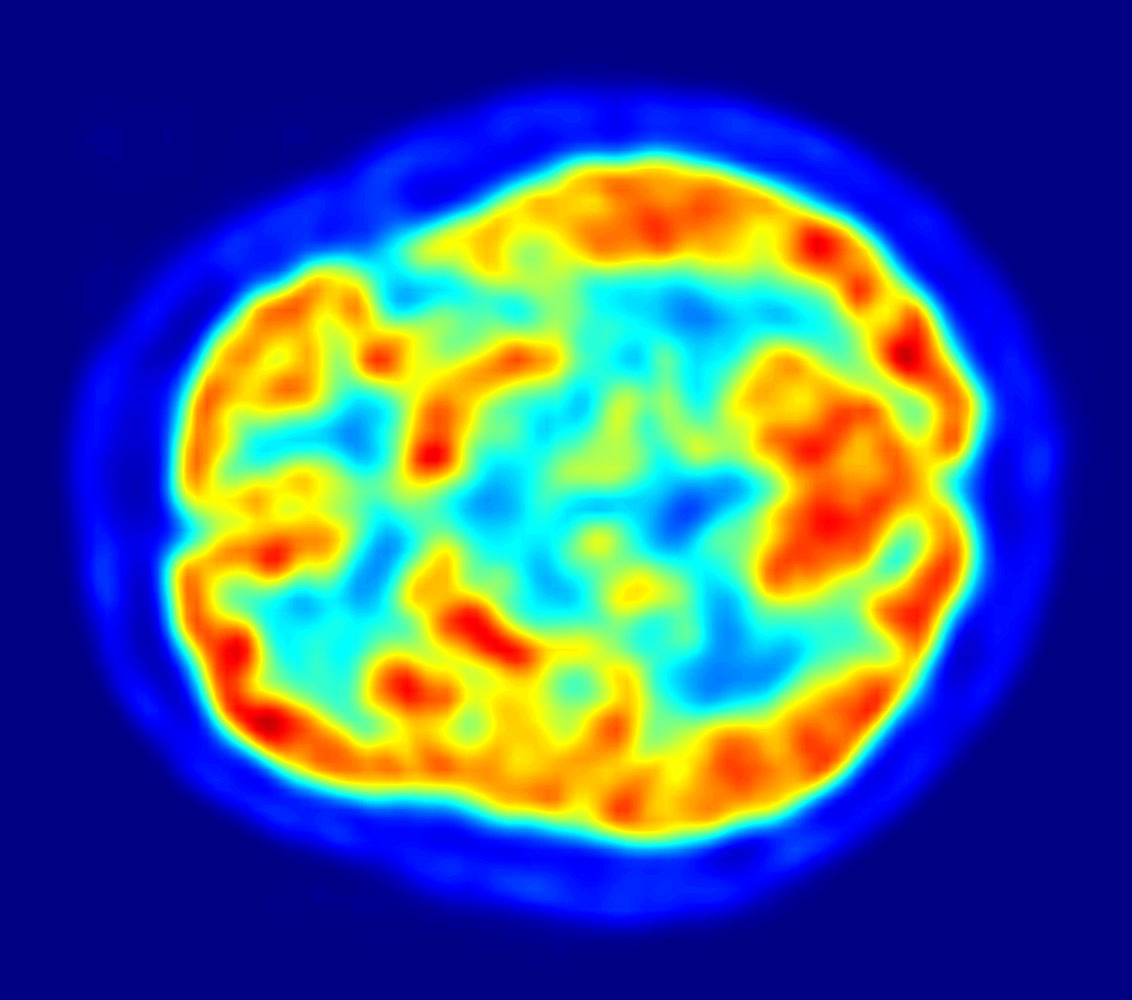

Fuente: Wikimedia Commons (enlace, dominio público), de Jens Maus